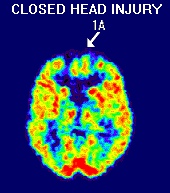

injury